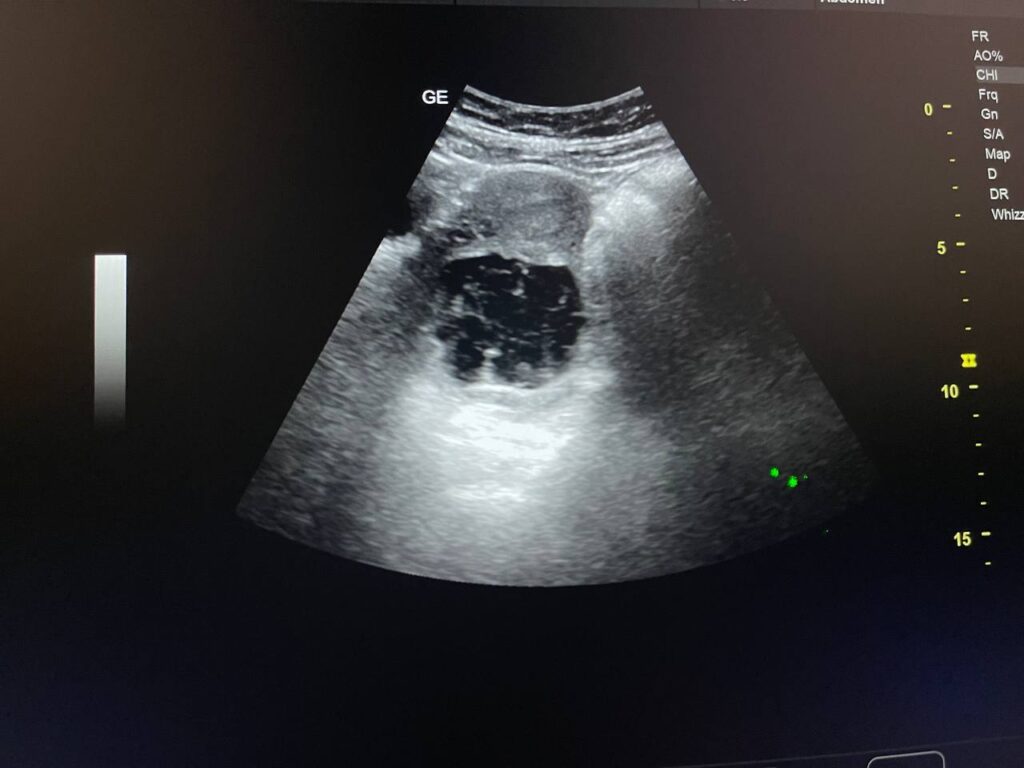

Right ovarian heterogeneous circumscribed avascular cystic mass its size 55x55mm, mostly hemorrhagic , with whirlpool sign , picture mostly of Twisted right hemorrhagic ovarian cystic , Cystic TORSION , please for further study ??

· No free pelvic fluid seen